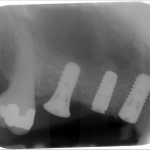

The bone used in a sinus lift may come from your own body (autogenous bone), from a cadaver (allogeneic bone) or from cow bone (xenograft). You will need X-rays taken before your sinus lift so the dentist can study the anatomy of your jaw and sinus. You also may need a special type of computed tomography (CBCT) scan. This scan will allow the dentist to accurately measure the height and width of your existing bone and to evaluate the health of your sinus.

Your surgeon will cut the gum tissue where your back teeth used to be. The tissue is raised, exposing the bone. A small, oval window is opened in the bone. The membrane lining the sinus on the other side of the window separates your sinus from your jaw. This membrane is gently pushed up and away from your jaw.

Granules of bone-graft material are then packed into the space where the sinus was. The amount of bone used will vary, but usually several millimeters of bone is added above the jaw.

Once the bone is in place, the tissue is closed with stitches. Your implants will be placed four to nine months later. This allows time for the grafted material to mesh with your bone. The amount of time depends on the amount of bone needed.